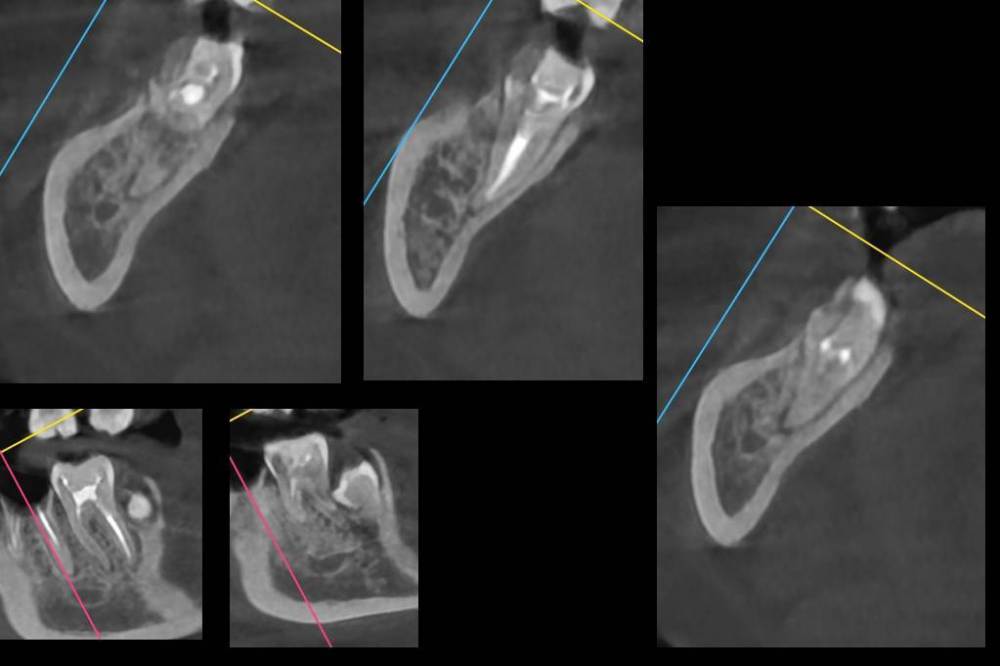

Множественные гранулемы и периодонтит зубов нижней челлюсти

8-ки растут в 7-ки, на корнях 7-ок, 6-ок, 45, 4-ок, 3-ек и 42 периодонтит.

Сказали, что 6, 7, 8 на удаление, остальные можно попробовать пролечить, но долго и без гарантий. И воспалительный процесс может вернуться в любой момент, как и обостриться.

P.S. Программа-просмотрщик с диска КТ наотрез отказалась устанавливаться на мой компьютер. Как сделать панорамный снимок в radiant я не поняла. Других просмотрщиков я не нашла. Так что не обессудьте... Как смогла так наскринила.